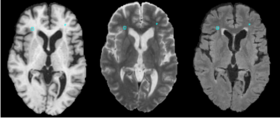

- The pipeline attempts to solve the problem of segmenting white matter lusions in lupus. The capability is aimed at clinical researchers.

- The state of the art is a work in progress in N-SLE. There are many approaches that attempt to solve lesion classification in Multiple Sclerosis. Some of these approaches are automated or semi-automated; however, all automatic approaches suffer a lack of a gold standard. It is difficult for humans manual raters to agree on fuzzy boundaries across different image constrasts (e.g., T1, T2, FLAIR).

- H. J. Bockholt, V. A. Magnotta, M. Scully, C. Gasparovic, B. Davis, K. Pohl, R. Whitaker, S. Pieper, C. Roldan, R. Jung, R. Hayek, W. Sibbitt, J. Sharrar, P. Pellegrino, R. Kikinis. A novel automated method for classification of white matter lesions in systemic lupus erythematosus. Presented at the 38th annual meeting of the Society for Neuroscience, Washingto, DC, 15 – 19 November 2008